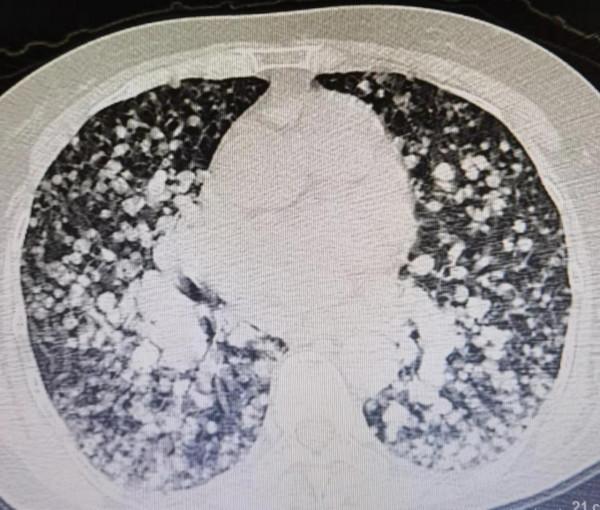

看到這個病人的胸部CT影象,我驚呆了,從醫這麼多年,真的沒見過這麼恐怖的影象,整個肺部就像滿布的雪花,又像蜂巢一樣千瘡百孔。可以說殘存的正常肺組織很少,全部被腫瘤佔據了。然而更為嚴重的是,腫瘤已經侵犯浸潤到氣管,她的氣管狹窄變扁,而咳血和氣喘主要也是由於氣管這裡的病變引起的。

這是這個病人的肺部CT:

這個病人是11年前患甲狀腺濾泡癌,當時做了甲狀腺部分切除手術,術後前兩年複查沒有太大問題,之後再也沒去過醫院,自己服用不清楚什麼成分的偏方,半年前就發現幹活之後氣喘,一直拖著沒去看,這次是咳血了才想起來到醫院檢查,這個肺部的影象屬實把大家都咋了一跳,“千瘡百孔”來形容一點不為過。這就是典型的肺轉移癌。這個病人已有呼吸衰竭的表現,需要立即吸氧,最後趕緊讓其到急診搶救。

肺部之所以容易成為癌細胞“安營紮寨”的地方,是因為肺迴圈的存在。全身的血液最終都要經過肺組織進行氣體交換,透過呼吸,把全身代謝的二氧化碳等廢物排出去,把氧氣吸入肺組織,進到肺血液再運到全身,所以肺迴圈血量非常大。全身不同部位的惡性腫瘤細胞都有可能透過血液迴圈最終轉移到肺部,就是我們通常看到的肺內轉移癌,而且肺內一旦發現轉移癌,多數都是多發的,呈實性的結節或腫塊,這些轉移結節往往是比較規則的圓形,影像學表現為胸片或CT上面很多多發的像棉絮狀的佔位性的病變。